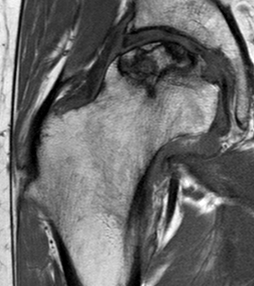

MRI

T1

T2

T2 Double Line Sign

Two lines virtually diagnostic of AVN

- outer line / low signa intensity

- inner line / high signal intensity / hypervascular granulation tissue